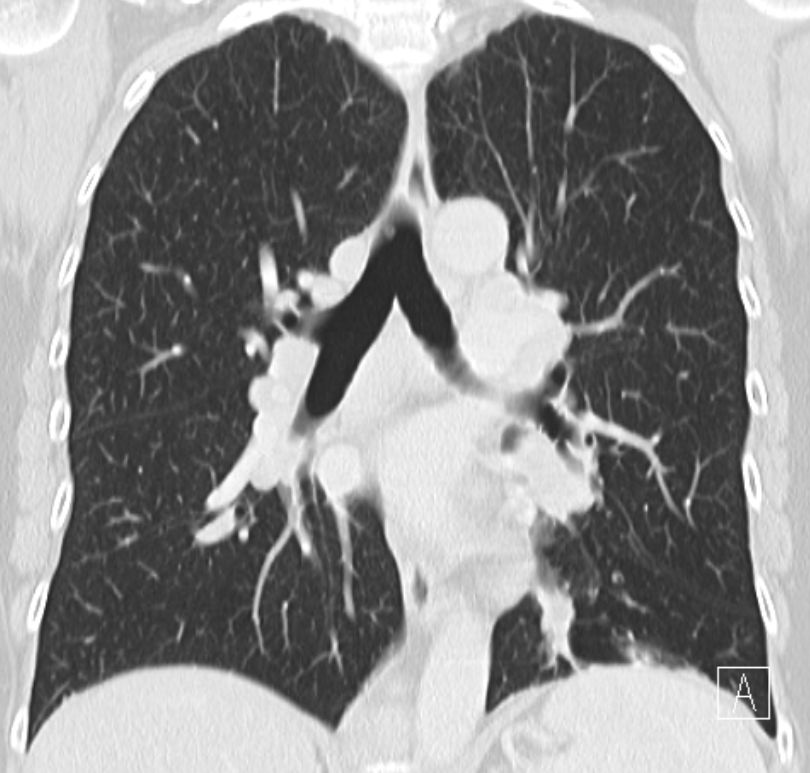

| Hilus- Lymphknoten | oft bihiläre Lymphadenopathie | 57-jährige Frau, die vor 15 Jahren ein Rektumkarzinom und vor einem Jahr ein Coecumkarzinom T4 N2b(14/14) Mo hatte. Beim Restaging vergrößerte Lymphknoten mediastinal, hilär beiderseits und paraaortal. Biopsie: floride Sarkoidose.![]() | |||||||||||||||||||||||||||||||||||||||||

| Lungen | mediastinale Lymphadenopathie | In 70% Lungeninterstitium befallen | Folge: Lungenfibrose. | ||||||||||||||||||||||||||||||||||||||||